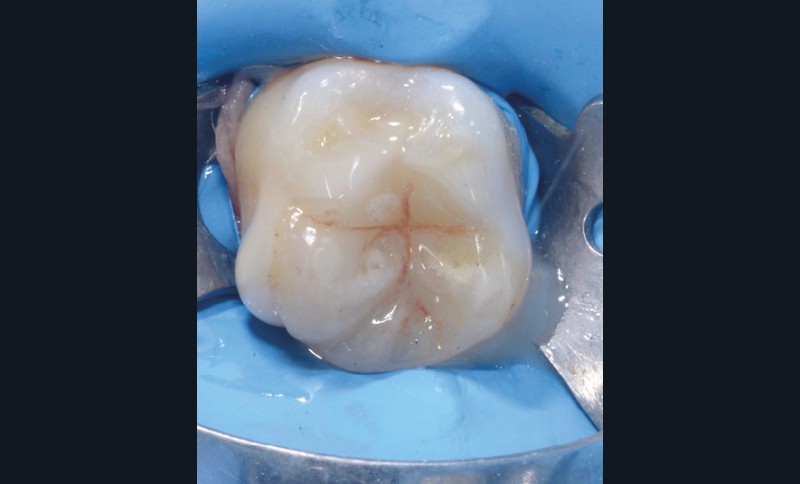

Lors de la préparation d’une cavité pour inlay/onlay, il est fréquent d’être confronté, en fin de nettoyage, à la présence d’une ou plusieurs parois résiduelles dont la résistance mécanique paraît douteuse du fait de leur localisation ou de leur épaisseur. Les parois épaisses (+ de 2 mm) peuvent généralement être conservées (cas clinique 1) et les parois fines (- de 1 mm) doivent généralement être recouvertes. Un inlay (en composite ou en céramique) est alors réalisé. Il doit avoir lui même, au final, une épaisseur globale minimale de 2 mm pour assurer sa résistance mécanique intrinsèque à la mastication. Si un recouvrement cuspidien est indiqué, la réduction occlusale doit donc se faire sur 2 mm de hauteur au minimum [1, 2].

Mais qu’en est-il des parois résiduelles d’épaisseur intermédiaire (entre 1 et 2 mm) (cas clinique 2) ?